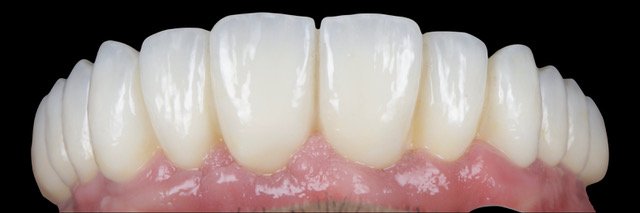

14.00 - 15.30 | Full arch implant reconstruction. From FP1 to FP3. How to plan a full mouth implant case. Digital workflow